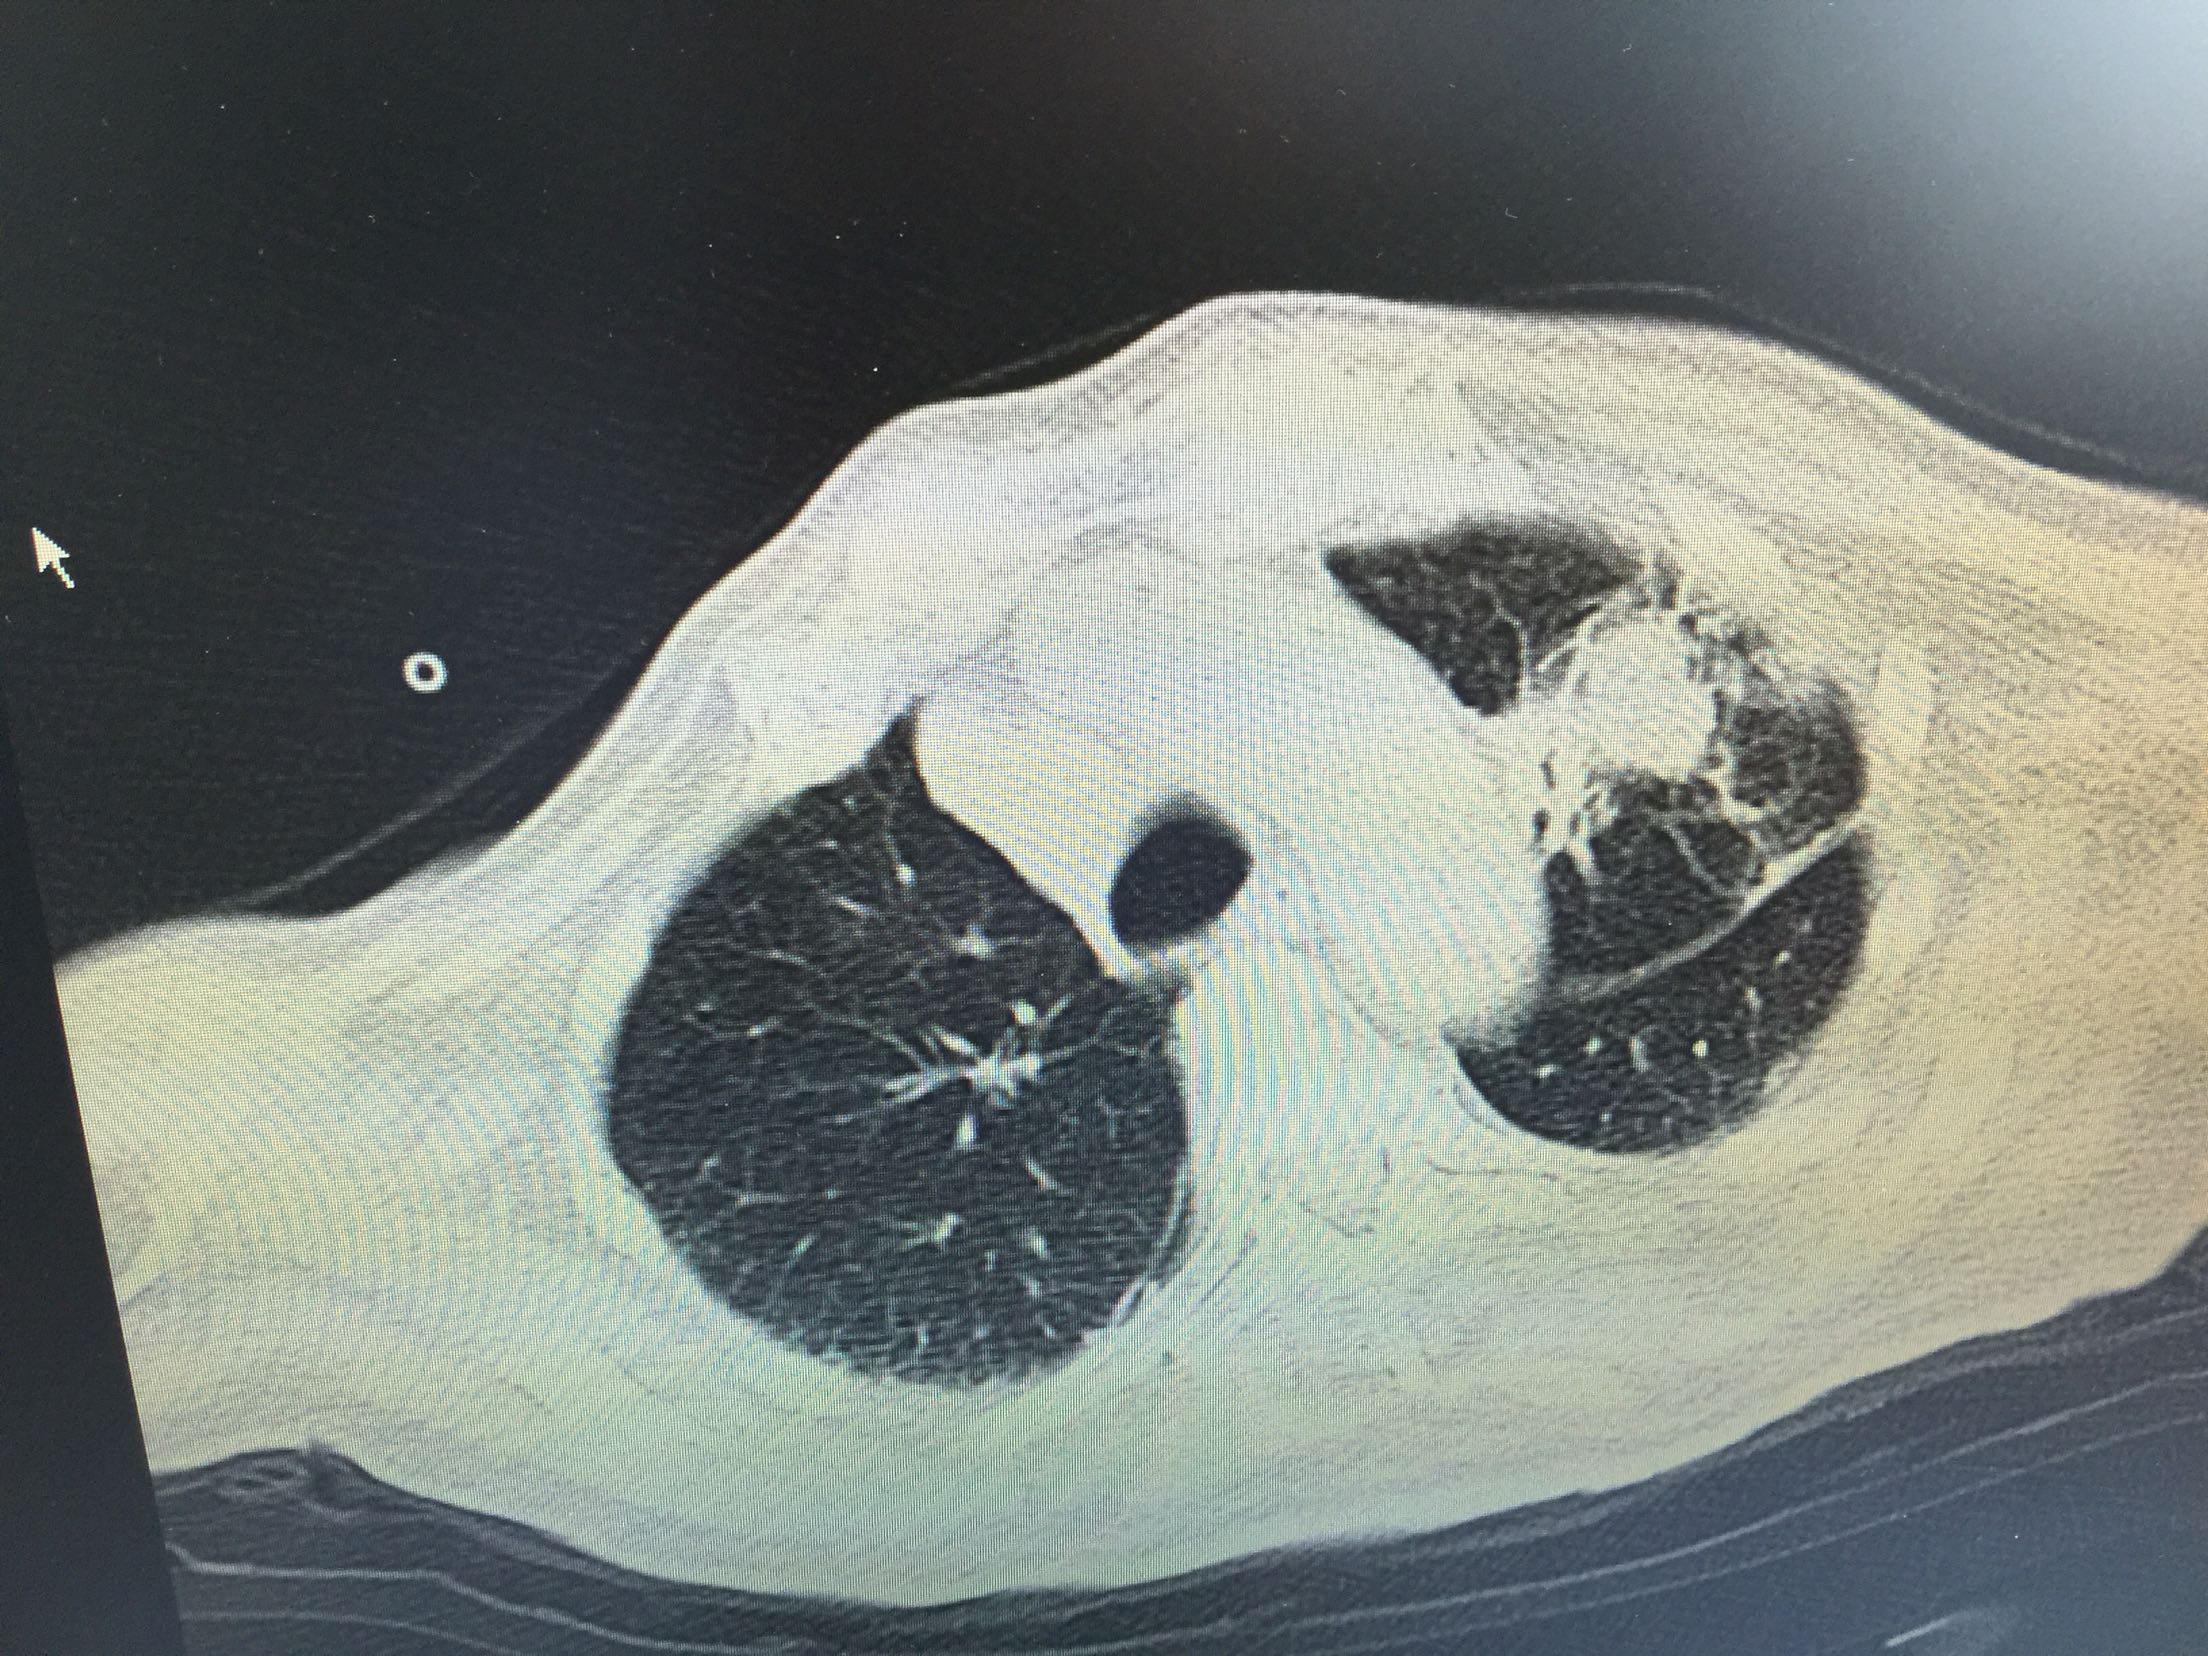

肺癌脑转移1例。

女,81岁,以“意识障碍1天”入院。

1.肺癌脑转移。 治疗:营养神经、脱水、抗感染、化痰、维持离子平衡治疗。